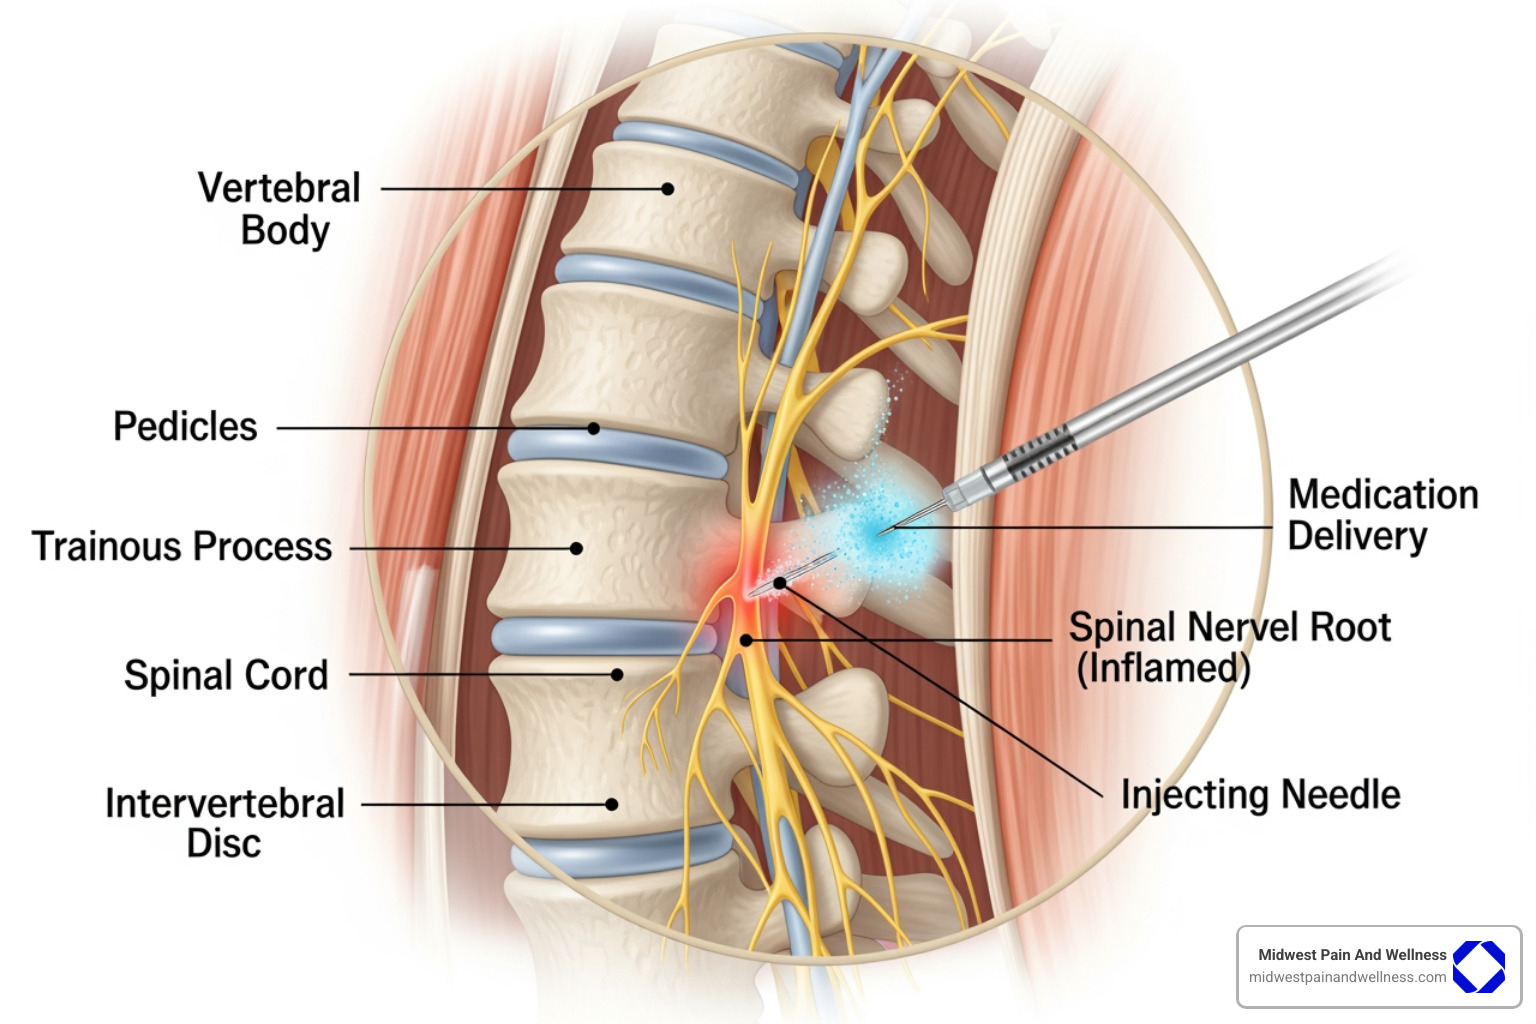

- Herniated Discs: When discs bulge and press on nerves, epidural steroid injections can calm the inflammation and radiating pain.

- Spinal Stenosis: This narrowing of the spinal canal puts pressure on nerves. Injections can ease the resulting inflammation and pain.

- Sciatica: For the shooting leg pain caused by a compressed nerve root, targeted injections can quiet the irritated nerve.

| Epidural Steroid Injections | Reduce inflammation and nerve irritation. | Epidural space (around spinal nerves). | Herniated discs, spinal stenosis, sciatica, nerve root compression, neck/back/arm/leg pain. |

- Epidural Steroid Injections (ESIs): When a herniated disc or spinal stenosis causes inflammation and pain that radiates down the arms or legs, ESIs deliver a corticosteroid into the epidural space around the nerves to provide relief.

Step 2: During the Injection

The injection itself is a straightforward outpatient procedure.

- Preparation: You will be positioned comfortably, and the injection site will be thoroughly cleaned and sterilized.

- Local Anesthetic: We numb the injection site with a local anesthetic to ensure your comfort during the procedure.

- Image Guidance: For precision and safety, we use advanced imaging like fluoroscopy (a real-time X-ray) or ultrasound. This allows us to guide the needle to the exact target location.

- Injection: Once the needle is perfectly positioned, the medication is slowly injected. You may feel a sensation of pressure, but not sharp pain.